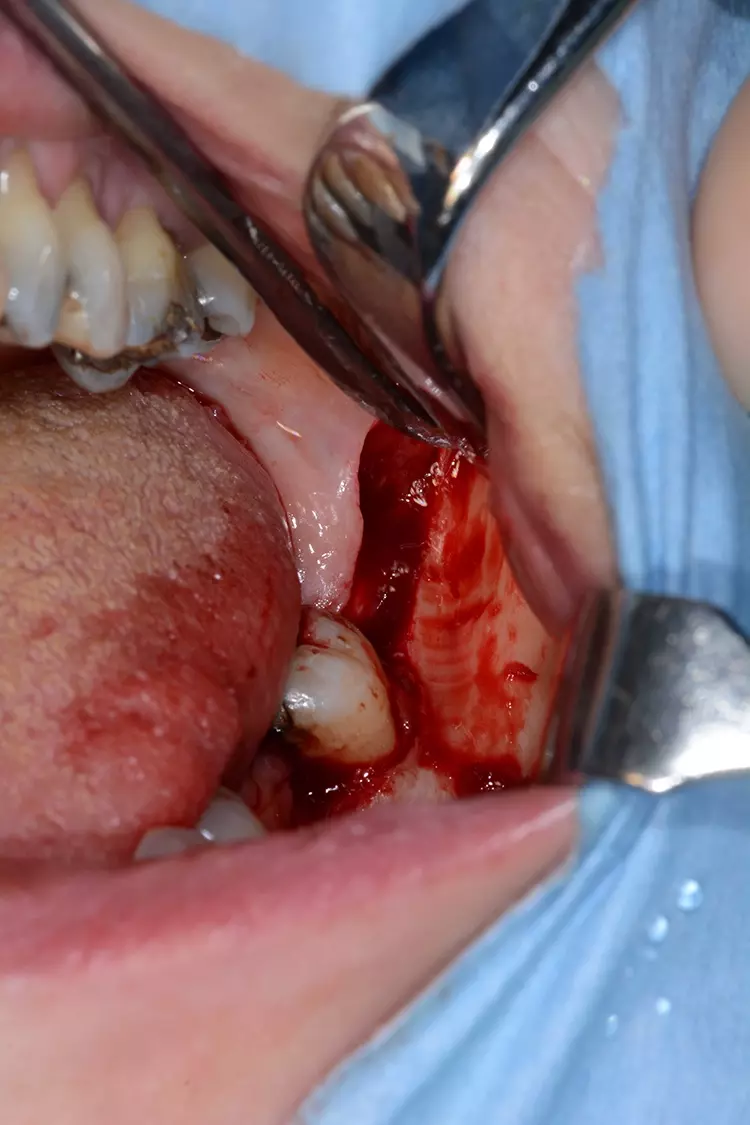

Chirurgisches Protokoll – 1. Sitzung

Der Wundbereich wurde mit monofilem, nicht resorbierbarem Nahtmaterial durch eine Kombination aus Rückstich- und Einzelknopfnähten vernäht (Abb. 6). In der klinisch postoperativen Kontrolle nach vier Wochen zeigte sich die Wundheilung komplikationslos (Abb. 7).